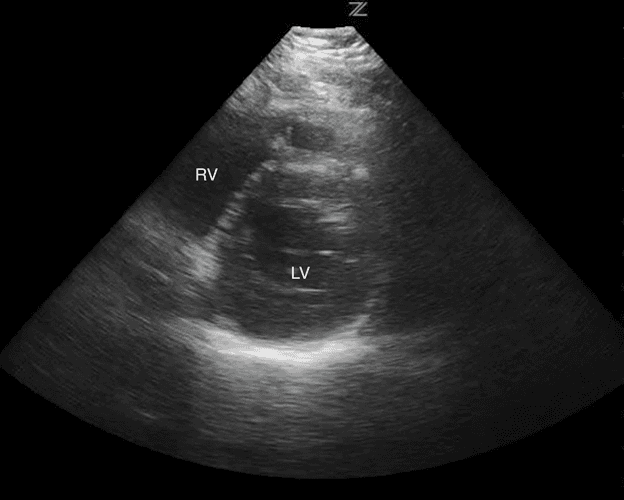

Esta vista permite la evaluación de la función del ventrículo izquierdo, la simetría de la compresión y la inclinación septal. El ventrículo izquierdo se puede identificar en esta vista y aparece como una circular en la parte inferior derecha de la pantalla. El ventrículo derecho aparece en forma de media luna y se encuentra en la parte superior derecha de la pantalla (Imagen 7).

Estructuras etiquetadas PSS